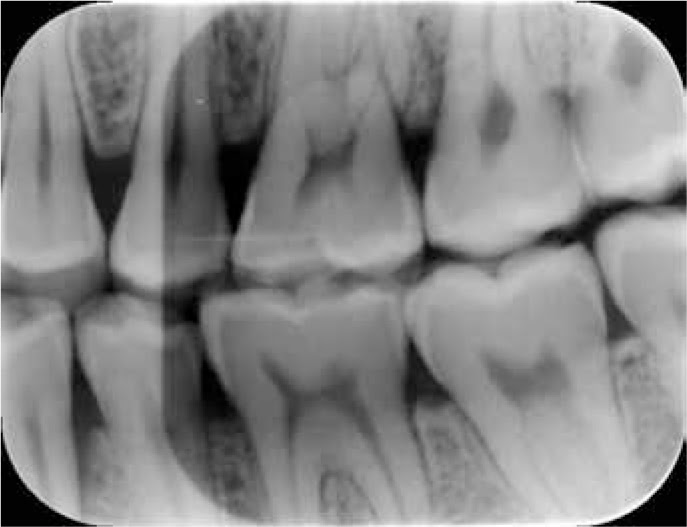

Quality assurance is a plan of action to ensure that a diagnostic x-ray facility will produce consistent high- quality images with a minimum of exposure to patients and personnel. Quality Assurance QA Many studies including those of the DPB have shown that up to 50 of dental radiographic images are of poor standard. The results should be discussed by radiation protection authorities in the context of the relevant legal requirements and current debates on radiation protection.

The phantom is ADA TR-1094 Report and AAPM. Click to see full answer. Quality assurance programmes for dental radiography are needed to ensure that images are consistently of a high standard.

All aspects of the imaging process must be monitored to reduce the number of repeat radiographs needed and to ensure radiography is carried out efficiently. Many dental X-ray equipment supply companies distribute Quality Assurance kits which include an attenuation step wedge a thermometer record keeping forms etc. Such kits may be useful in setting up Quality Assurance programs.

Quality assurance is a plan of action to ensure that a diagnostic x-ray facility will produce consistent high- quality images with a minimum of exposure to patients and personnelFewer repeat radiographs mean time and cost savings for both patients and operators. Image quality On a monthly basis images produced using either a PSP or a SSD should be compared with a good quality reference image.